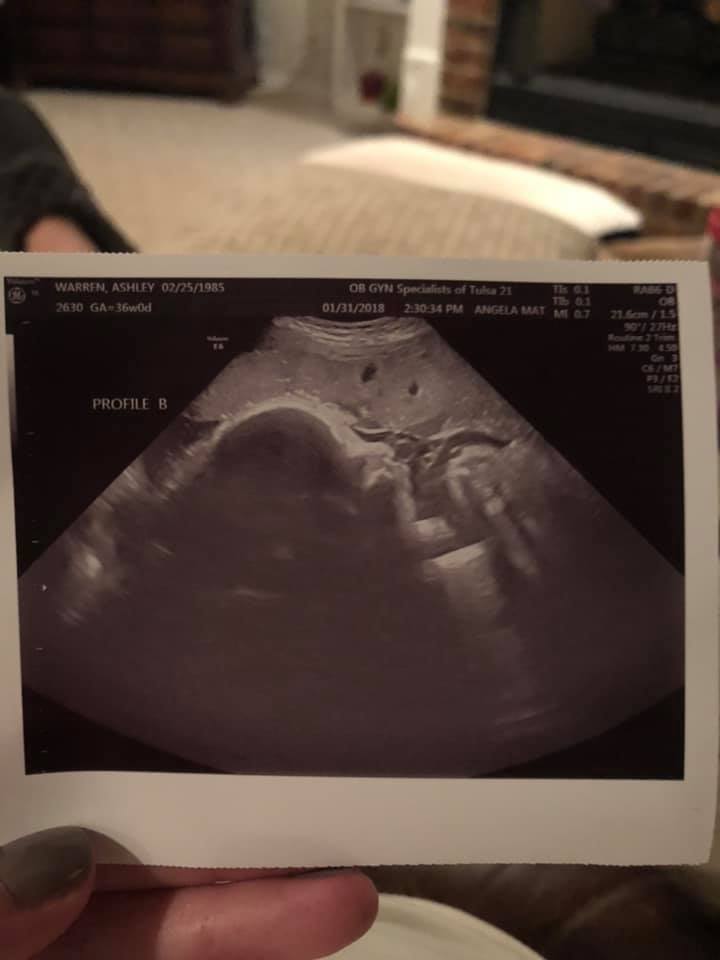

- Ultrasound Photos at 36 Weeks Pregnant With Twins

Ultrasound Photos at 36 Weeks Pregnant With Twins